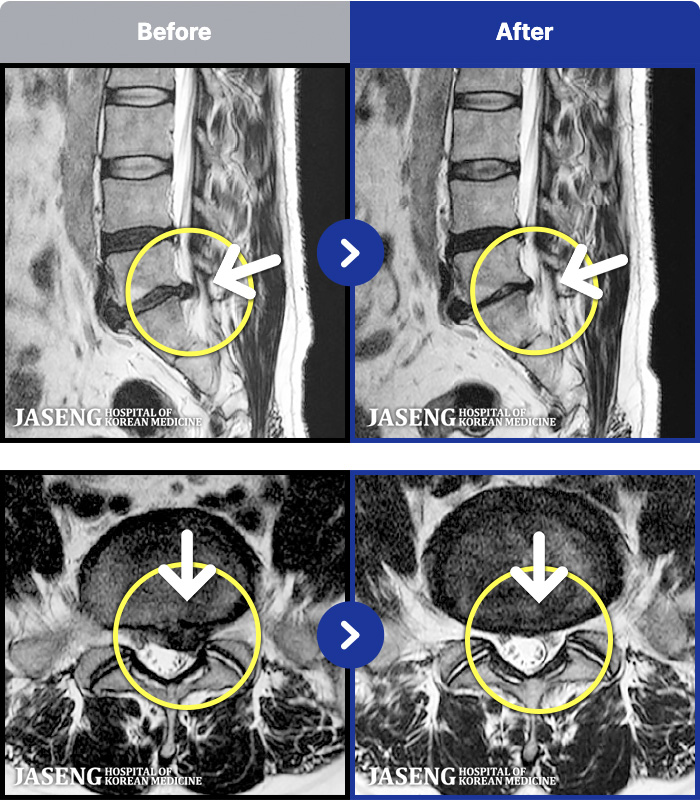

1,299 MRI ũ ʸ Ȯϼ.

[] 23.11.11~25.06.04